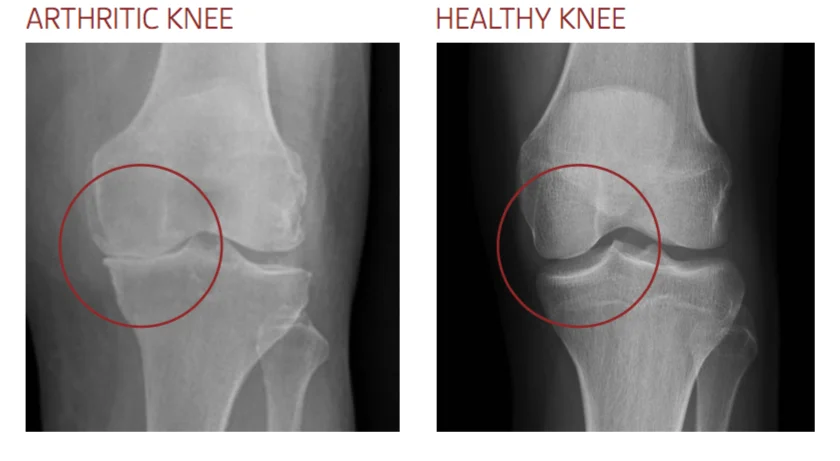

Osteoarthritis

The most common cause of knee pain. In osteoarthritis, the cartilage that cushions the bones wears away, causing: